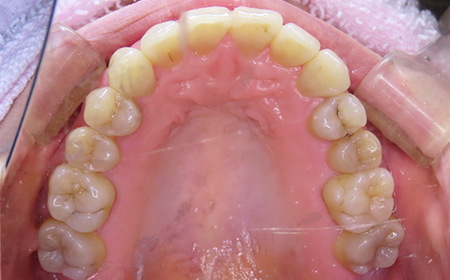

CASE08

Before

After

| 施術名 |

インビザラインコンプリヘンシブを用いた矯正治療(叢生) |

| 治療期間 |

1年 |

| 治療費 |

880,000円(税込) |

| リスク |

マウスピース装置により疼痛・咬合時痛を生じる事があります。割れたり壊れたりする事があります。 |

歯科医師からのコメント

「上顎八重歯が気になる」で来院されました。分析すると、軽度なねじれでしたのでインビザラインGoにて治療をすすめていきました。マウスピースを積極的に使用し、順調に治療がすすんでいきました。仕上がりにとても満足しておられました。